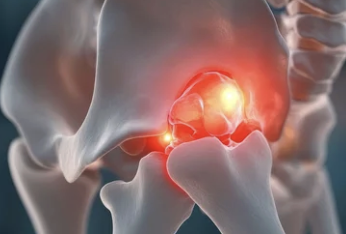

1️⃣ 슬개골 탈구란 무엇일까?

강아지의 무릎(슬개골)은 대퇴골 홈 안에 위치해 있어

다리 움직임을 안정적으로 도와주는 역할을 합니다.

하지만 이 슬개골이 제자리를 벗어나면,

관절이 어긋나면서 통증과 보행 이상이 생기죠.

💡 쉽게 말하면:

무릎뼈가 옆으로 ‘툭’ 빠지는 상태예요.